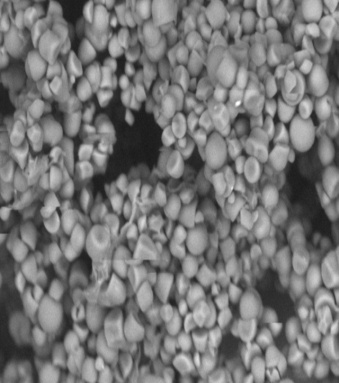

SEM images

SEM images were taken for Jack fruit seed powder, Telmisartan pure drug, JFS2, CCS, a blend of Telmisartan with JFS2 and a blend of Telmisartan with CCS. It was observed that the starch grains in Jack fruit seed powder were covered with some mucilage or resinous mass which were clearly represented in the image. The JFS2 starch exhibited a free-flowing spherical low dense form of starch grains without any mucilage/resinous coverage. Telmisartan pure drug exhibited crystalline form. CCS exhibited blunt tubular-shaped crystals. The SEM image of Telmisartan with JFS2 clearly exhibited uniform dispersion of drug with spherical globular starch grains. The SEM image of Telmisartan with CCS showed uniform dispersion of drug with blunt tubular crystals of CCS. The complete adhesion of natural agent with drug enhances solubility property of the poorly water-soluble drug. This was also supported by the earlier studies [18]. The detailed SEM images were shown in fig. 5.

Fig. 5: SEM Images: (A) Jack fruit raw seed powder (B) JFS2 (C) Telmisartan, (D) CCS (E) A blend of Telmisartan and JFS2 (F) A blend of Telmisartan and CCS; JFS2–Jack fruit seed starch extracted by 0.1% sodium hydroxide; CCS–Croscarmellose sodium